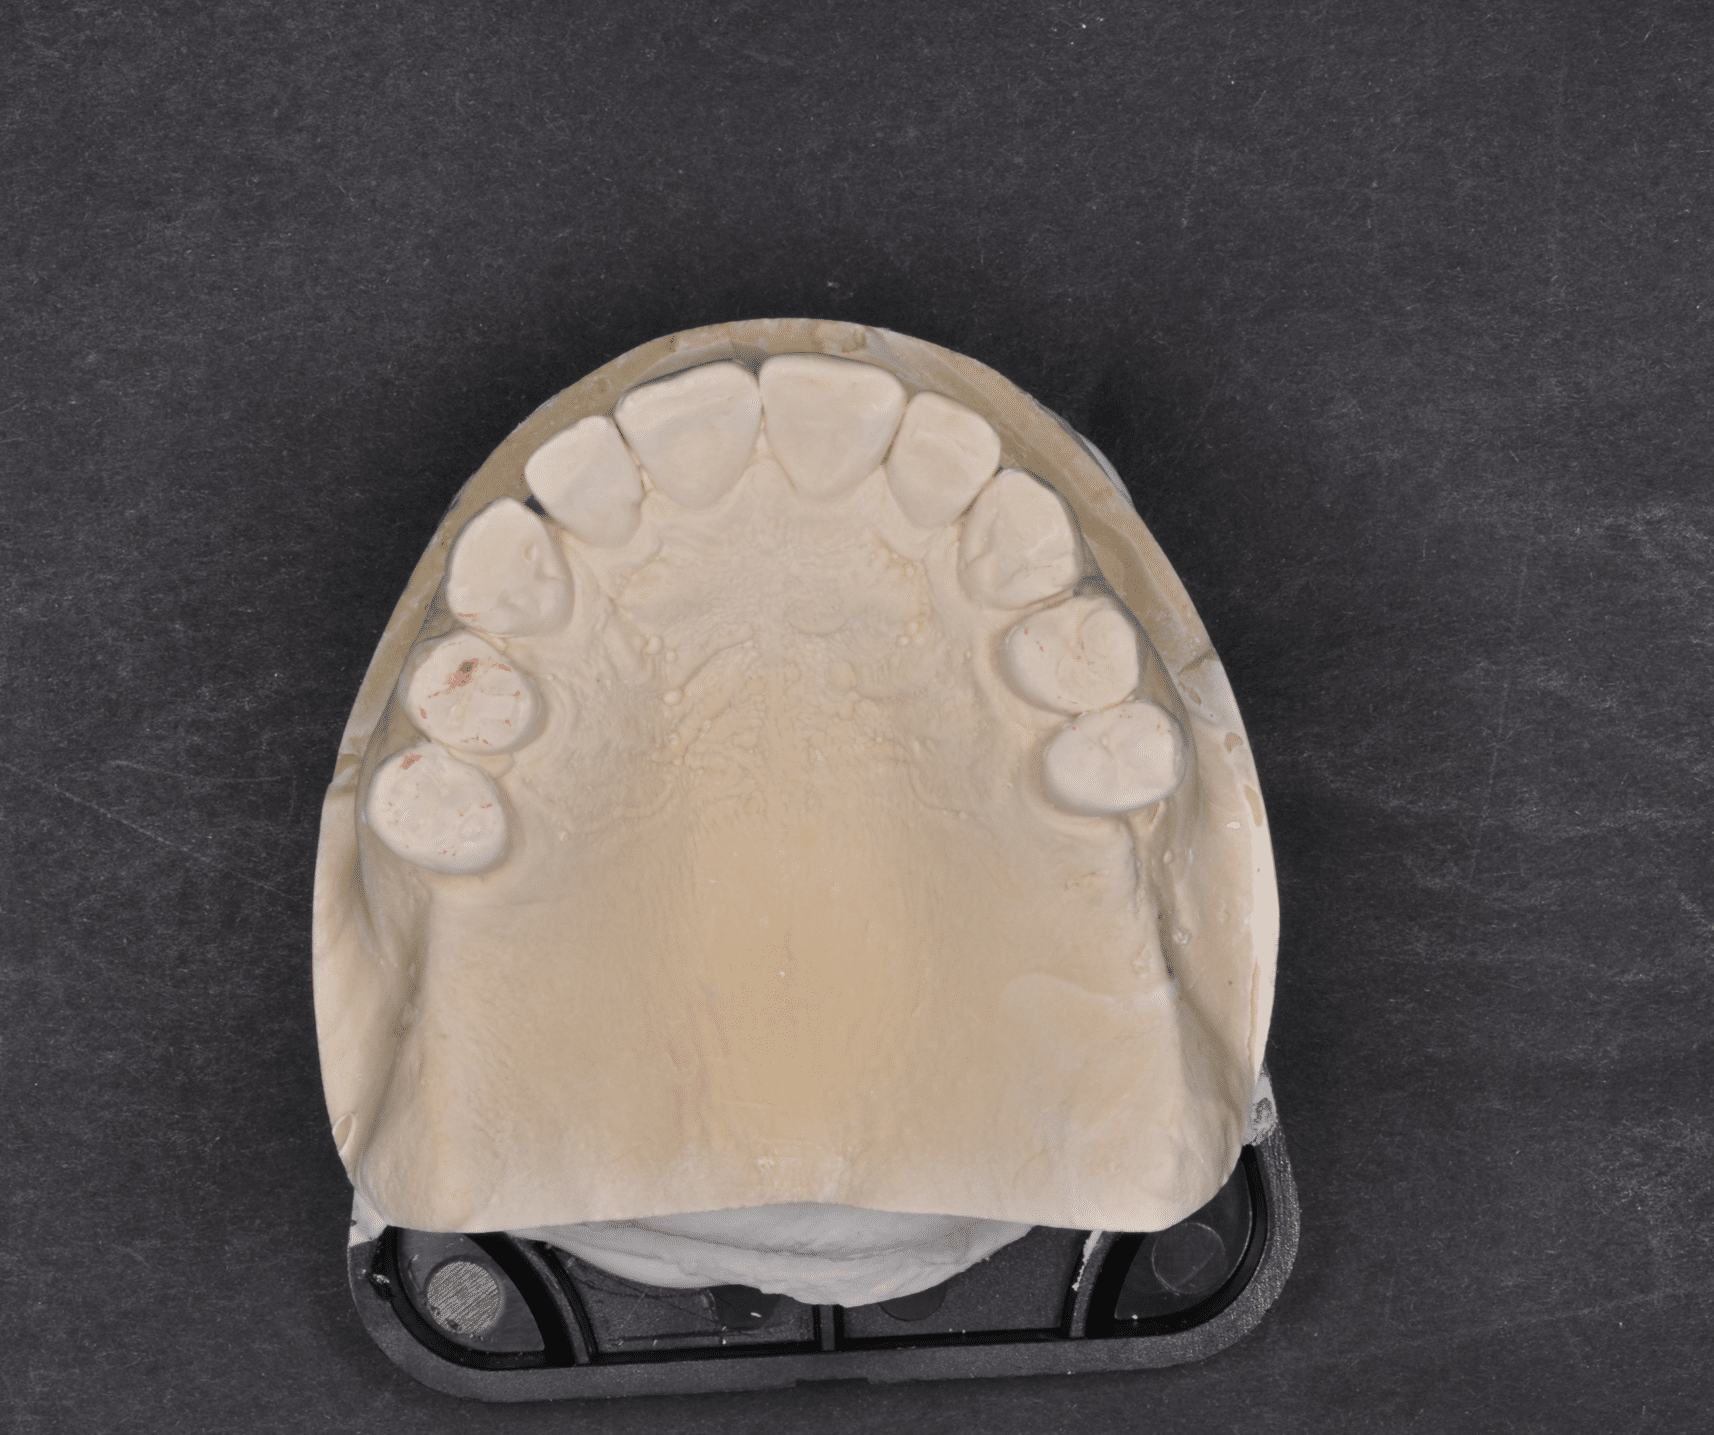

Împreună cu pacientul, am optat pentru inserarea implantelor cu ajutorul ghidului chirurgical pentru a plasa implantul în poziția protetică ideală și pentru a permite realizarea coroanelor insurubate pe implant. A fost efectuată scanarea digitală a arcadelor și a ocluziei pacientului, iar împreună cu tehnicianul radiolog de la DigiRay a fost suprapus fișierul .stl al amprentei digitale peste fișierul .dcm de la CBCT, utilizând software-ul 3Shape.

Doar astfel putem crea profilul de emergență corect al coroanei dentare, ceea ce permite conformarea papilei și a sulcusului.